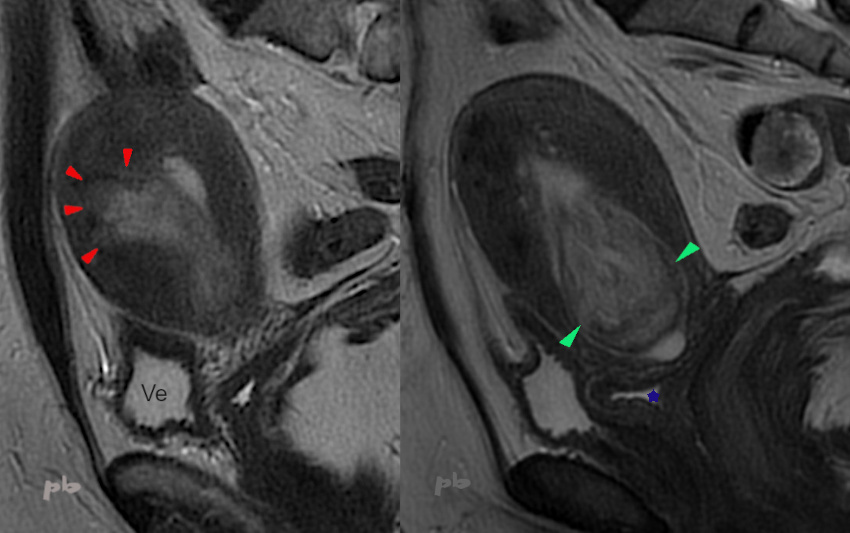

IRM – Coupes sagittales T2.

On suit ce volumineux polype depuis sa base d’implantation (►) au niveau du fond utérin, jusqu’à sa tête en intra-cervical (►). Il présente un aspect plus hétérogène et une taille nettement plus importante que les cas précédents. Surtout l’interface floue au niveau de l’implantation pourrait être interprétée comme une infiltration de la paroi.

Ve = vessie

Cul de sac vaginal antérieur contenant un peu de liquide (★)